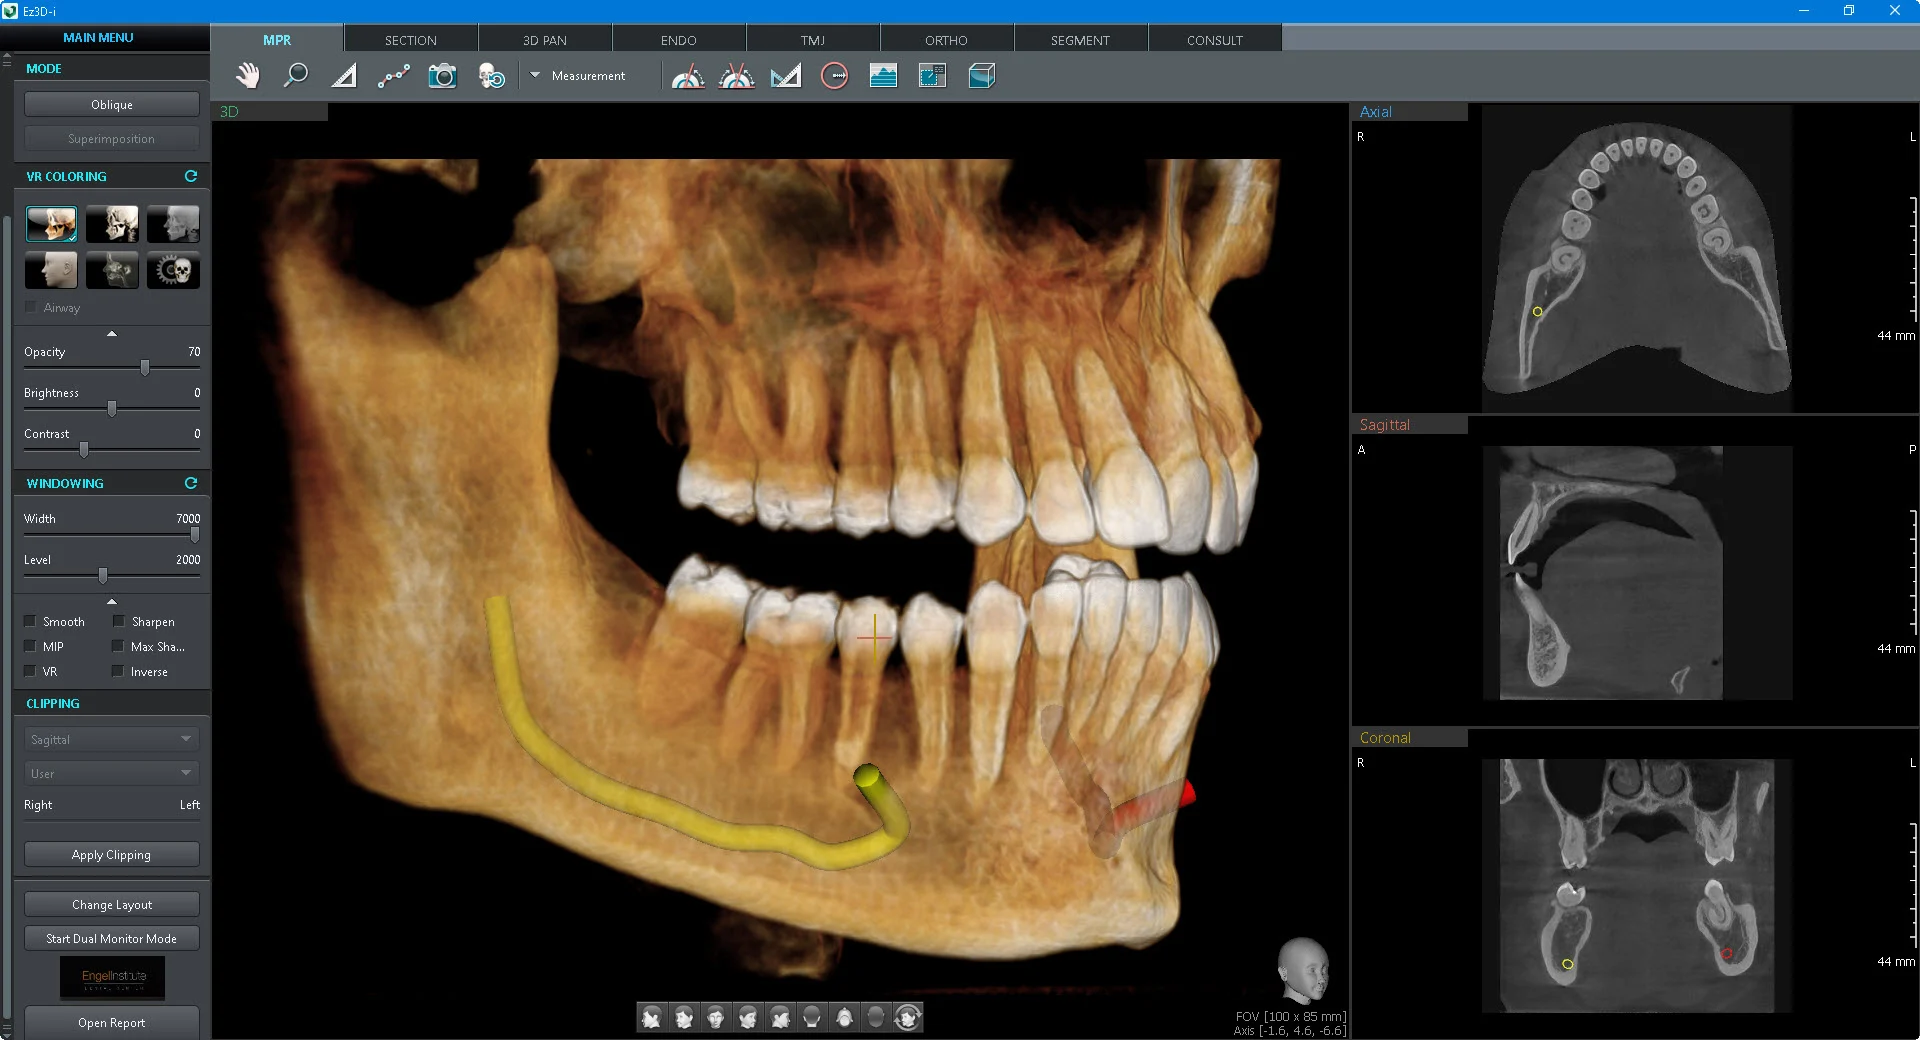

CBCT (Cone Beam Computed Tomography) в Fibo Diagnostic Center — это высокоточное 3D-исследование зубочелюстной системы за один визит.

Мы используем современное оборудование, позволяющее получать детализированные снимки с минимальной лучевой нагрузкой. CBCT даёт полное представление о состоянии зубов, костных структур, корней и суставов.

3D-снимок одной или обеих челюстей в высоком разрешении.

Файлы в формате, совместимом с любым CAD/CAM ПО.

Вы получите интерактивный 3D-снимок, на котором чётко видны: зубы и корни, костные структуры челюсти, гайморовы пазухи, суставы ВНЧС.

Файл можно просматривать в специализированных программах или передать вашему врачу/лаборатории для планирования лечения.

Как выглядит результат?

Фотореалистичная 3D-модель лица

Возможность виртуальной примерки будущих конструкций;

Возможность рассматривать результат под любым углом.